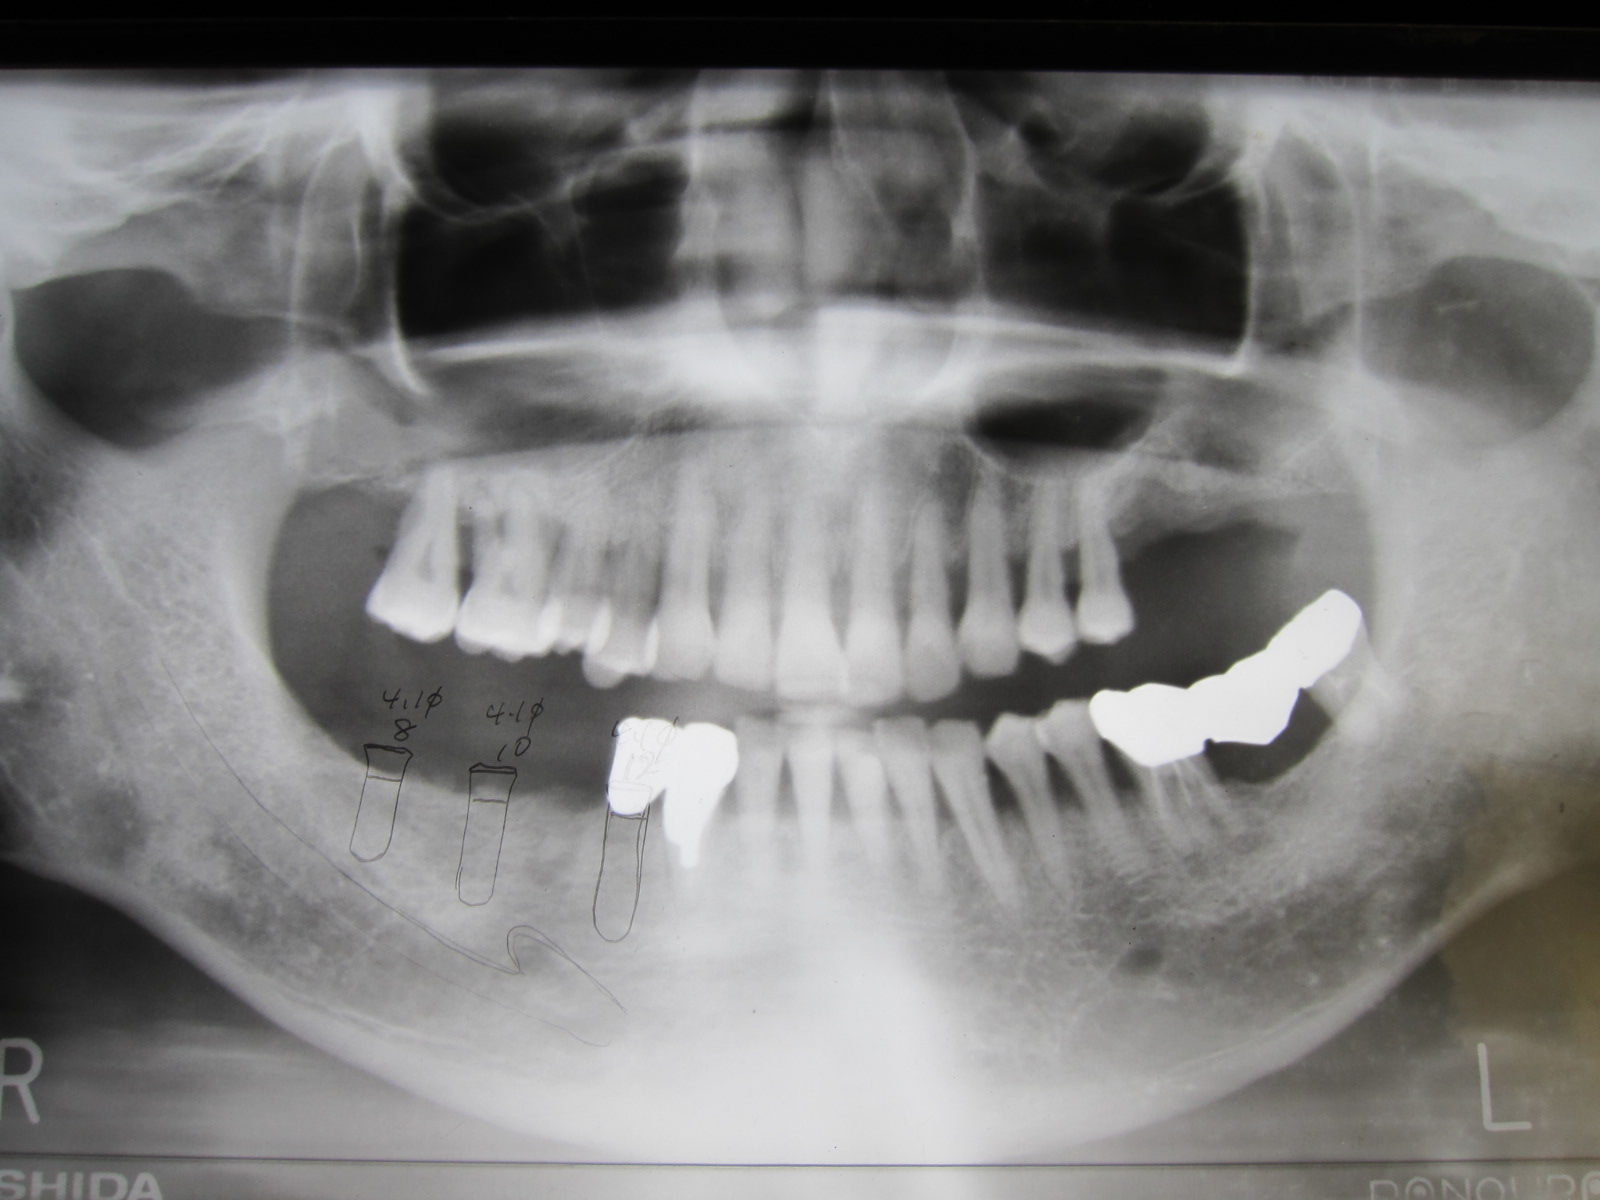

9年前の初診時、右下にインプラントの埋入を計画した時のレントゲンです。

平成16年に初診で来院され、右下の奥歯に3本のストローマンインプラントを植立し、4ユニットのブリッジを装着しました。